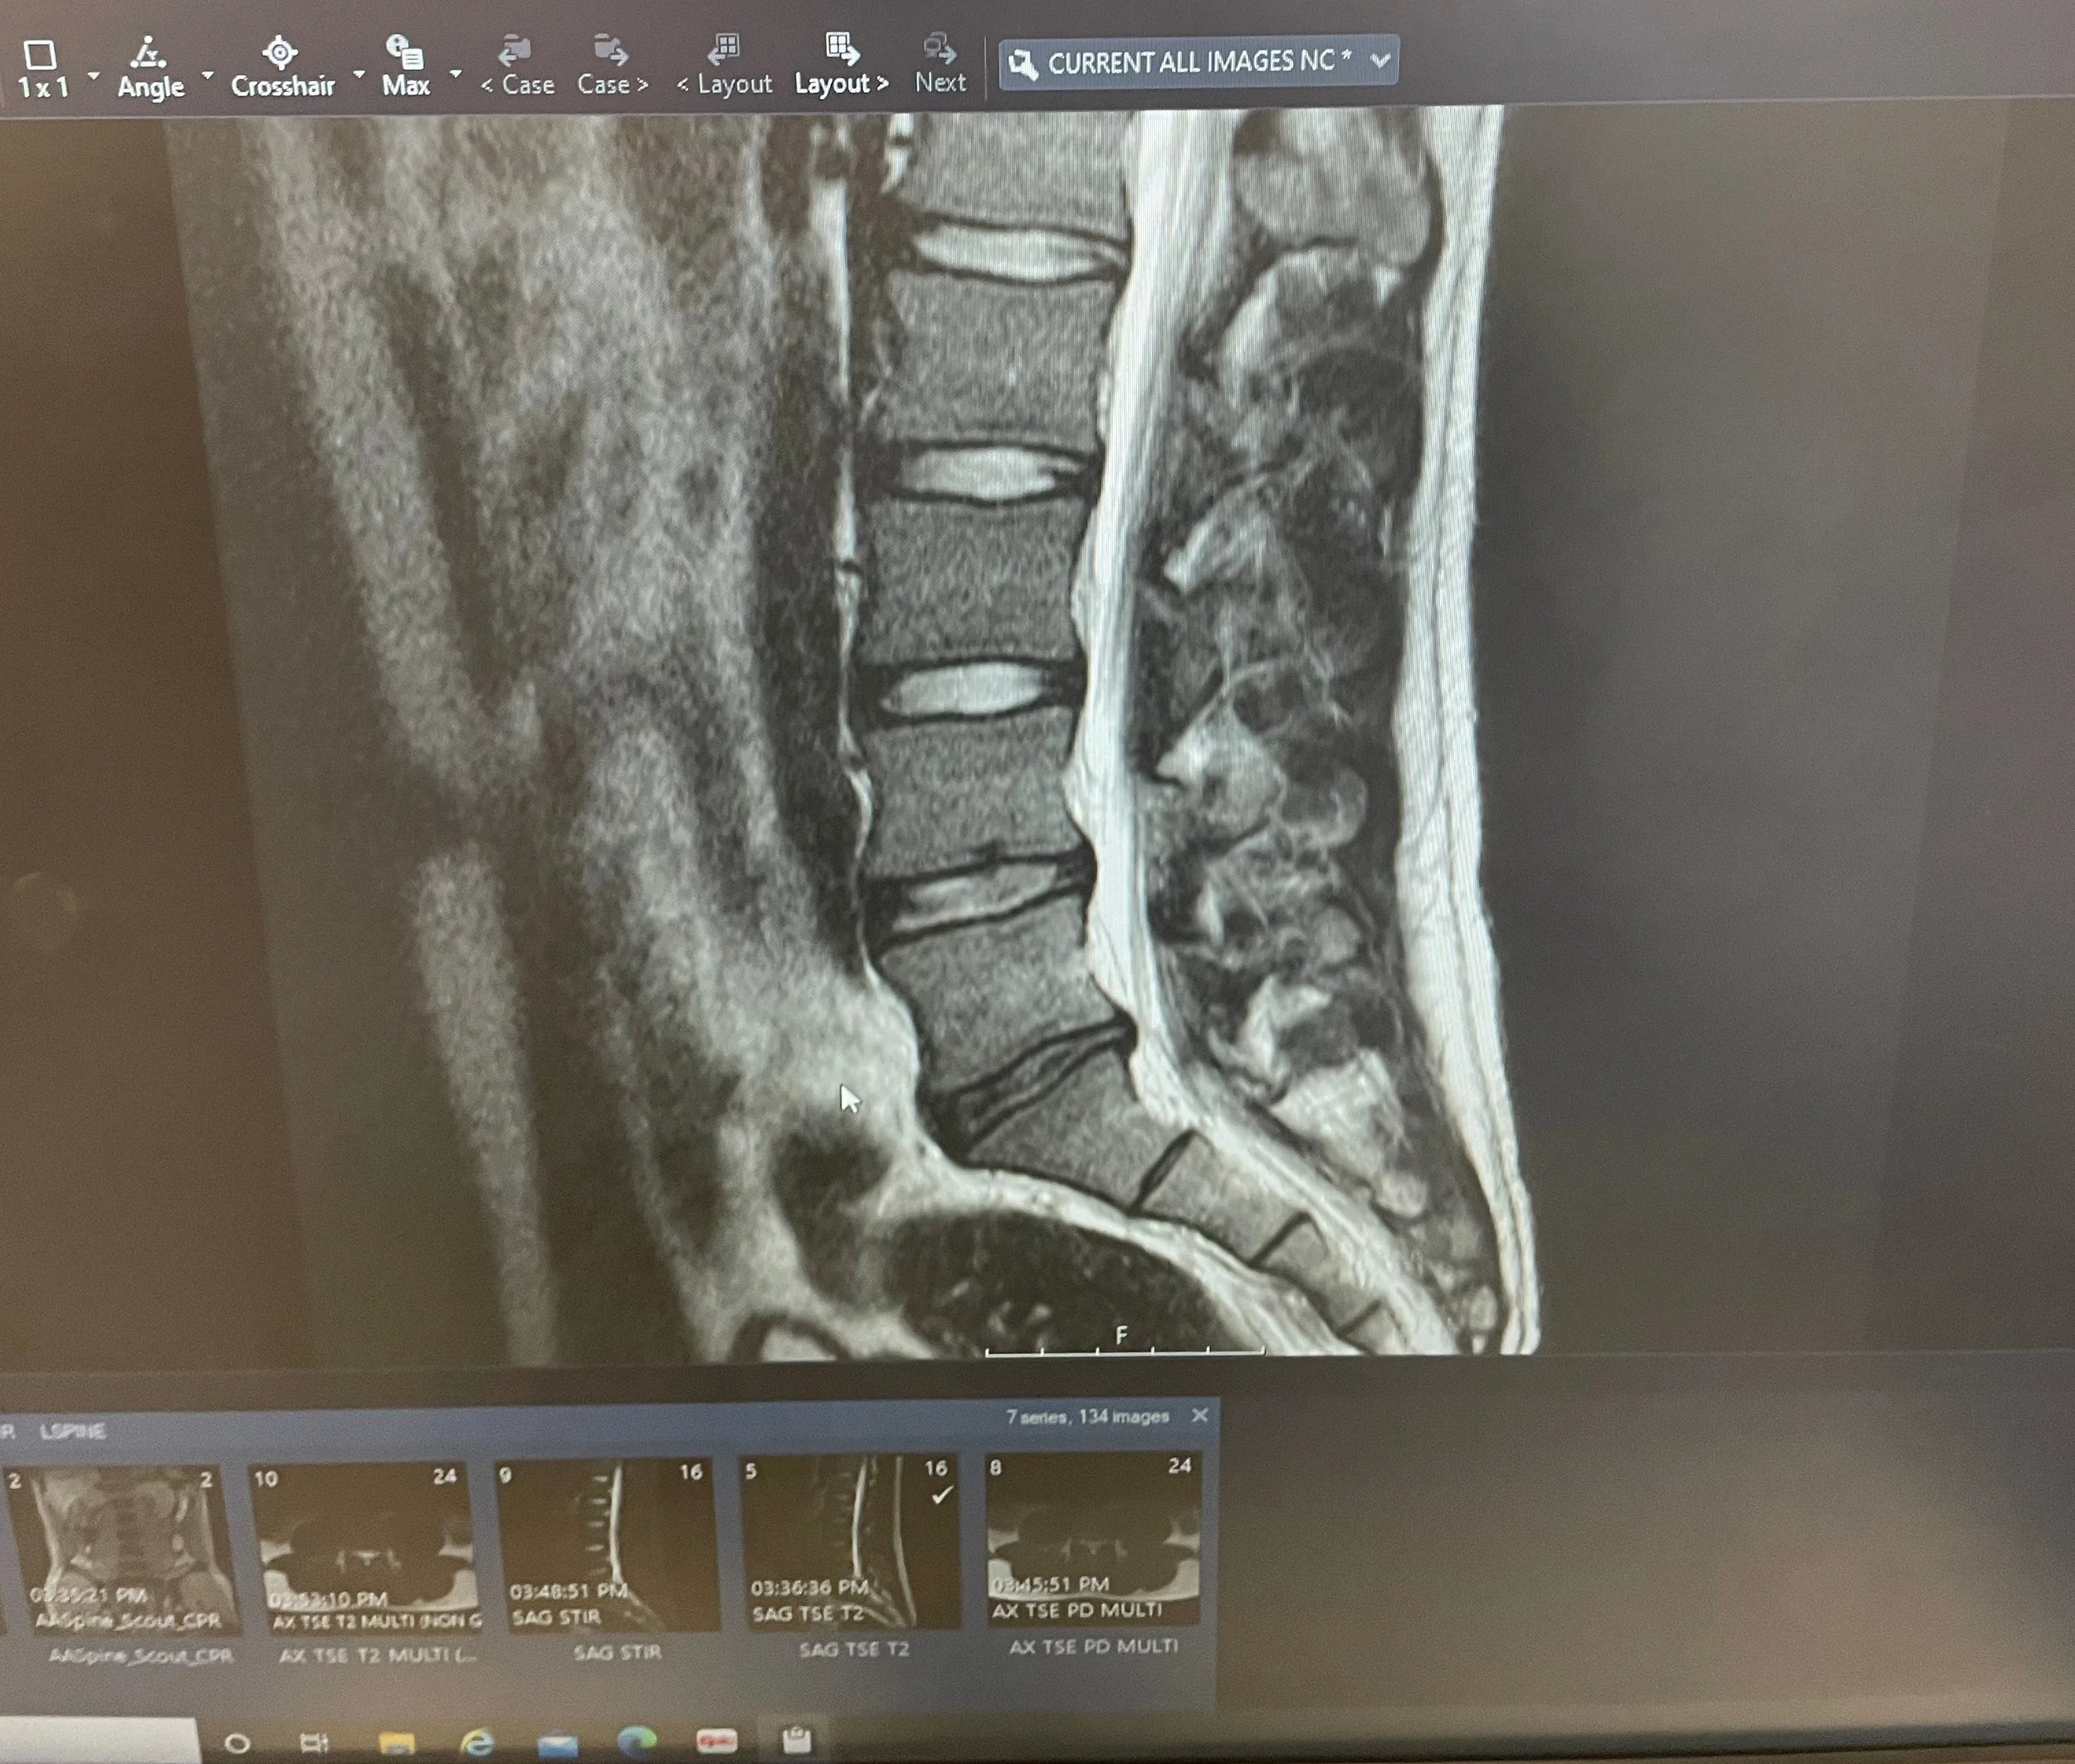

Unfortunately I had a serious lower back injury playing tennis that forced me to stop playing competitively and when it first happened I was actually paralyzed from my left hip down for several hours and didn’t know if I’d even be able to walk again. I was honestly terrified and in agony. It was the most excruciating pain I’ve ever felt.

MRI scan of the lumbar spine showing vertebrae, discs, and spinal canal.